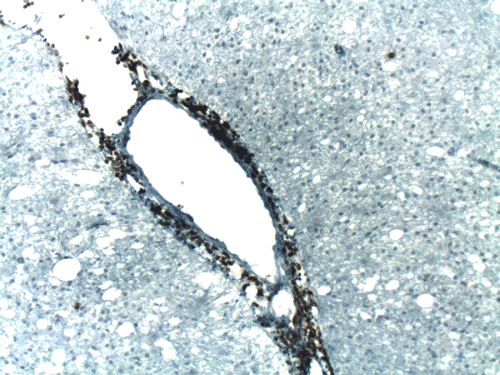

On CT scan, there is multiple hypodense white matter lesions that appear to spare a thin layer of subventricular white matter (Panel A). The T2-weighted images on MRI provides a more accurate estimation. The white matter in the occipital lobes is most affected (Panel A). There is extensive vacuolar changes in the white matter (Panel B and C) and there is a questionable increase in cellularity. In some of the thin walled blood vessels, there is a thin layer of perivascular lymphocytic infiltration which is free of atypia (Panel D, E, and F). The lymphocytes do not appear to extends into the parenchyma. On higher magnification, some large reactive astrocytes can be seen (Panel G). In a minority of areas, some concentric rings can be seen on hematoxylin-eosin stained sections (Panel H). These rings appear to be alternating rings of myelinated and demyelinated white matter and the vacuolar changes appear to be limited mainly to the concentric lesions. The adjacent myelinated areas are spared (Panel I). In some areas, the level of myelin loss appears to be proportional to the level of vacuolar changes (Panel J and K). On immunohistochemistry for glial fibrillary acidic protein (GFAP), the degree of gliosis is also more impressive in areas with more prominent vacuolar changes (Panel L and M). The vacuolar areas also appear to have a reduced density of axons (Panel N). Axonal spheroids are also present in these areas (Panel O). Although a prominent infiltration of foamy histiocytes is not noted on hematoxylin-eosin stains, immunohistochemistry for CD68 illustrated positive cells in a minority of demyelinated areas (Panel P). These cells lacks the foamy nature of macrophages and their morphology would suggest microglial cells. The reactive astrocytes are not immunoreactive for CD68 (Panel Q). Immunohistochemistry for T-cells (CD3) and B-cells (CD20) demonstrates only a thin rim of perivascular infiltration without significant extension into the surrounding parenchyma (Panel R, S, and T).

Pathology

On histology, there are extensive spongiform degeneration and vacuolar degeneration of the deep white matter associated with variable macrophage, profound axonal loss, degenerating axons with spheroid formation and evidence of axonal injury in adjacent normal appearing white matter  1, 2, 3, 4. Demyelinating changes featured by lost of myelin and infiltration of macrophages have also been described  1,  2, 5,  6. Under the electronic microscope, there are vacuolar degeneration of the oligodendroglia, swollen mitochondria and distended endoplasmic reticulum.